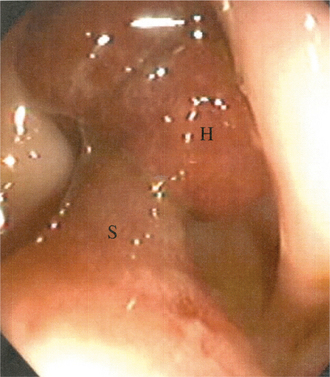

This disease has a well-defined sequence of events. The stepwise progression of this cancer often occurs over many years and begins with a polyp, a collection of cells on the lining of the large intestine. At first, there is an aberrant proliferation or hyperplasia of cells, which leads to a particular type of polyp called benign adenoma, containing abnormal but not malignant cells. Then the cells transform to carcinoma in situ, and finally to metastatic carcinoma. This process is thought to be due to a series of genetic mutations within the cells.42 Some benign polyps may regress and disappear over time, but most continue to undergo changes that transform them into malignant tumors (Fig. 16-20).

Figure 16-20 Large pedunculated polyp in the rectum. The stalk (S) itself is benign, with the head (H) containing the adenomatous tissue. The polyp was removed safely in a one-step endoscopic procedure. (From Goldman L: Cecil textbook of medicine, ed 22, Philadelphia, 2004, Saunders. Courtesy of Pankaj Jay Pasricha.)